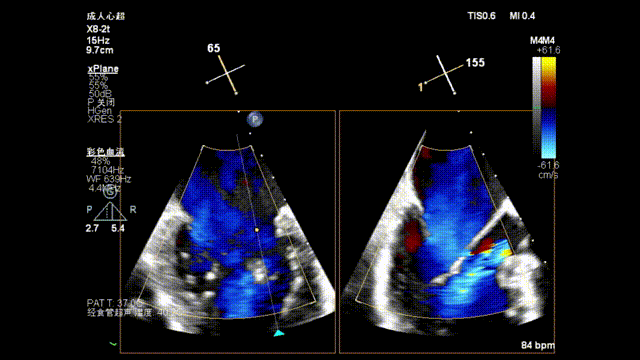

瓣上M/L和A/P调整瓣膜夹,在X-plane进行超声确认,

瓣上进行前后瓣对应夹片确认

3D指示下调整瓣膜夹朝向病变区域P2偏P3区